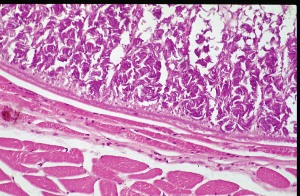

Section of sheep oesophagus infected with Sarcocystis

This is a high power view of a section through a tissue cyst of Sarcocystis. This view shows the outer region of the cyst with groups of bradyzoites arranged around the supporting framework of the cyst.